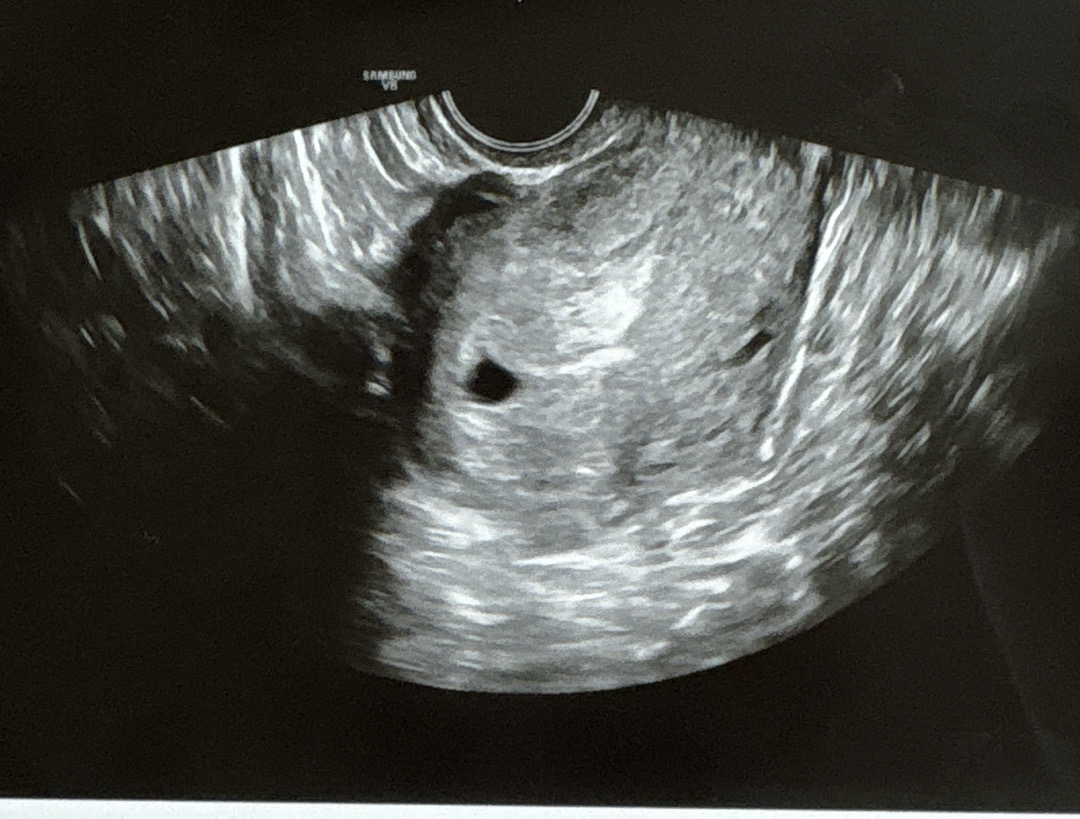

9월 23일에 난포 터지는 주사 맞고 10월 17일에 아기집 보고 왔는데요. 오늘 10월 27일에 난황 보러 갔는데, 아기집에 아무것도 안 보인다고 하더라구요ㅠ 근데 챗지피티는 왼쪽 위에 난황이 보인다고 하고ㅠㅠ 우선 일주일 후에 다시 초음파 보기로 했는데 저랑 같은 경우였던분 계실까요?

보이는 것 같구, 저것도 확대할수록 난황이 더 잘 보이더라구요? 너무 염려되시면 병원에서 다시 초음파 찍으시던가 선생님께 여쭤보세요!! 선생님이 제일 정확하니까요 :) 너무 걱정마세요!!

왼쪽위에 조그만하게 난황있어요

난황보이는걸요~~왼쪽위에~